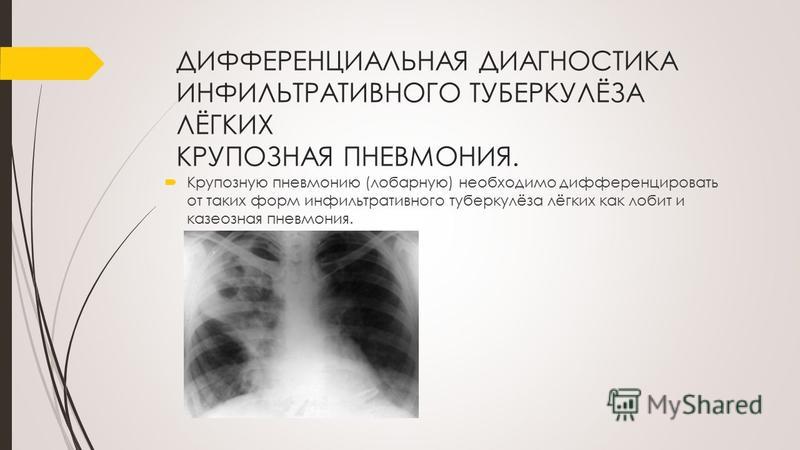

Симптомы и лечение инфильтративного туберкулеза легких

Раздел: Снимки-откровения